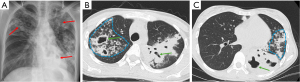

Cavitation occurs in approximately 4% of metastatic nodules identified on radiographs, compared to a higher frequency of 9% observed in primary bronchogenic carcinoma (12). Squamous cell carcinoma is considered the most common cell type associated with cavitating metastases; however, cavitation can also occur in metastatic nodules arising from adenocarcinomas and sarcomas (Figure 3) (12). Seo et al. even reported that the incidence of cavitation in metastatic nodules observed on CT imaging was similar between adenocarcinoma and squamous cell carcinoma histologic types (12).

The development of cavitation may also result from therapeutic interventions such as chemotherapy or radiotherapy applied to lung malignancies, with the underlying cause believed to be either tumor necrosis or a check-valve mechanism resulting from tumor infiltration into the bronchial structures (12).